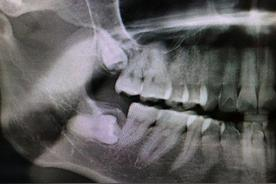

那為什么醫生會說她的智齒需要拔呢?一看片子,好家伙,這四顆牙齒雖說茁壯成長,但也確實是在各長各的,難怪醫生說要拔。

第三個,長的不正。

智齒阻生

如果只是長的不太整齊,但不影響其他牙齒,我們或許可以忍受,但我朋友有一顆盡頭牙是橫著長的,醫生說這叫阻生,阻生牙的力量很大,會推著其他牙齒往前擠,難怪她覺得讀書時候牙齒挺齊的,年紀越大牙齒卻越來越不整齊,那可能就是盡頭牙在“作怪”。

她的情況還比較嚴重,盡頭牙抵著前面一顆牙齒的牙根和牙冠,醫生告訴她,一天兩天沒感覺,但等到牙齒會疼的時候,問題就大了,到時候就兩顆牙都保不住。